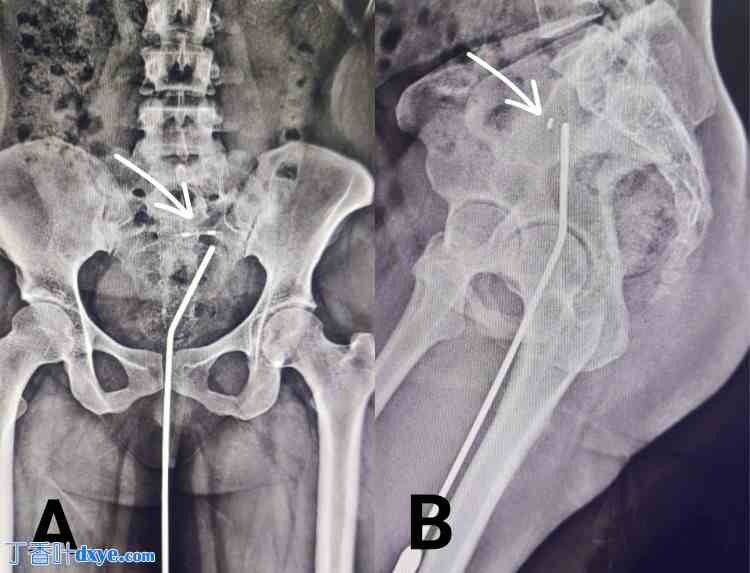

在初次盆腔检查中,发现宫内节育器的线在宫颈口处未见,这引发了对该节育器位置的担忧。患者还透露,她曾去当地一家医疗保健机构就诊,该机构试图取出宫内节育器,但只取出了一部分(垂直臂和线)。为了确认宫内节育器在宫腔内的位置,医生进行了宫内探子原位X光检查,结果确认宫内节育器位置正确,如图1所示。

图1. 宫内探子原位盆腔X光检查。 (A) 前后位图和 (B) 侧位图。白色箭头标示宫内节育器的位置。